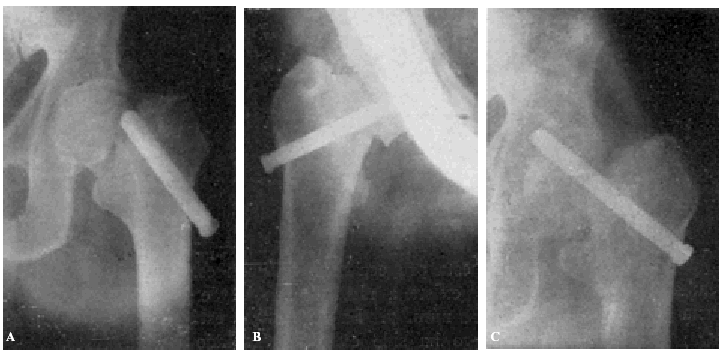

Teniendo en cuenta el mal estado general de la enferma se procede a la tracción continua, con ocho kilos de peso, mediante el procedimiento de Kirschner. A los ocho días ha mejorado extraordinariamente el estado general de la enferma, procediendo entonces a la osteosíntesis. Hay que advertir que la radiografía anteroposterior ha sido practicada antes de la completa penetración del clavo (fig. 2., A y B).

Figura 2. A: obs. núm. 8. Radiografía practicada antes de la completa penetración del clavo. Este está colocado en una posición demasiado craneal. B: Obs. núm. 8. El clavo fue colocado siguiendo la dirección del Kirschner superior. C: obs. núm. 8. El clavo se ha salido de la cabeza por su parte superior y su punta está situada a nivel de la parte superior de la caja cotiloide.

La radiografía (fig. 2., C) demuestra que el trocáncer ha ido ascendiendo, cortando el clavo el hemisferio superior de la cabeza hasta que, por haber chocado con la ceja cotiloidea, la ascensión del trocánter se ha detenido; pero entonces la pelvis ha basculado, ascendiendo la cresta ilíaca de este lado.

Actualmente nuestra mayor experiencia nos permite afirmar que el clavo, en este caso, había sido colocado demasiado cranealmente, y que, con toda probabilidad, una mejor exploración del estado general de la enferma nos hubiera indicado la inoperancia de la intervención.